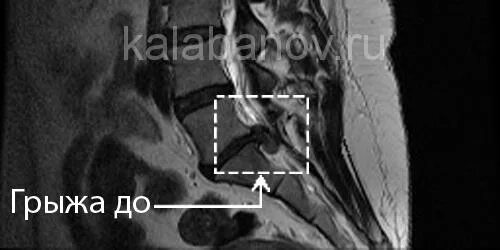

Дексаметазон при грыже позвоночника поясничного